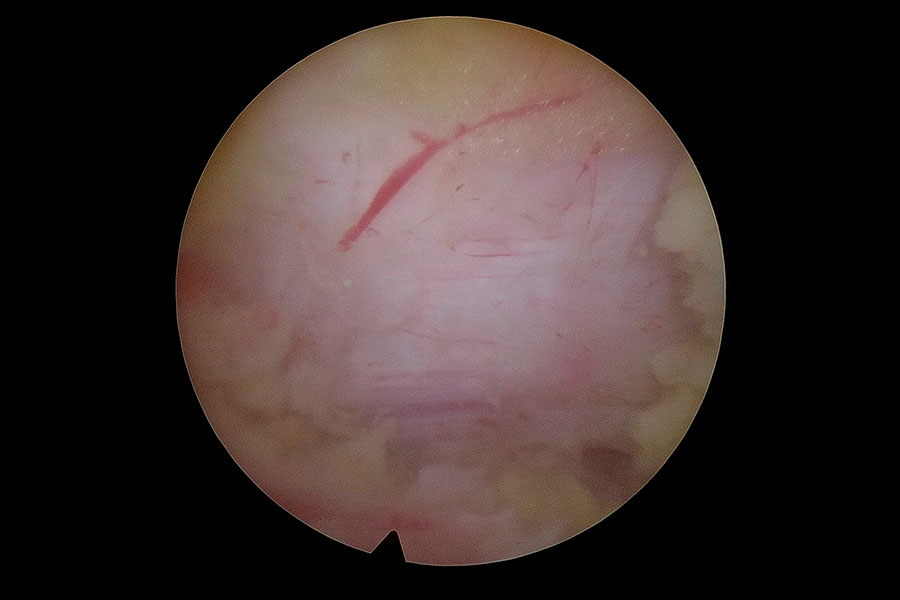

Caso clínico: endoscopia de columna multinivel L4L5 y L5S1

Los síntomas que presentaba el paciente eran dolores acentuados en las piernas, claudicación a la marcha y calambres y hormigueos en las piernas.

Durante la intervención quirúrgica, se abordarán los dos niveles mediante la técnica de endoscopia de columna.